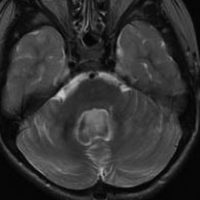

手術翌日のMRIです。小脳失調症状の出現はなく,抜糸してすぐに退院して普通の生活に戻れました。

この画像を見れば,後頭下開頭テント下法 infratentorial approach では,小脳切断しなければ腫瘍に届かないことが理解できると思います。